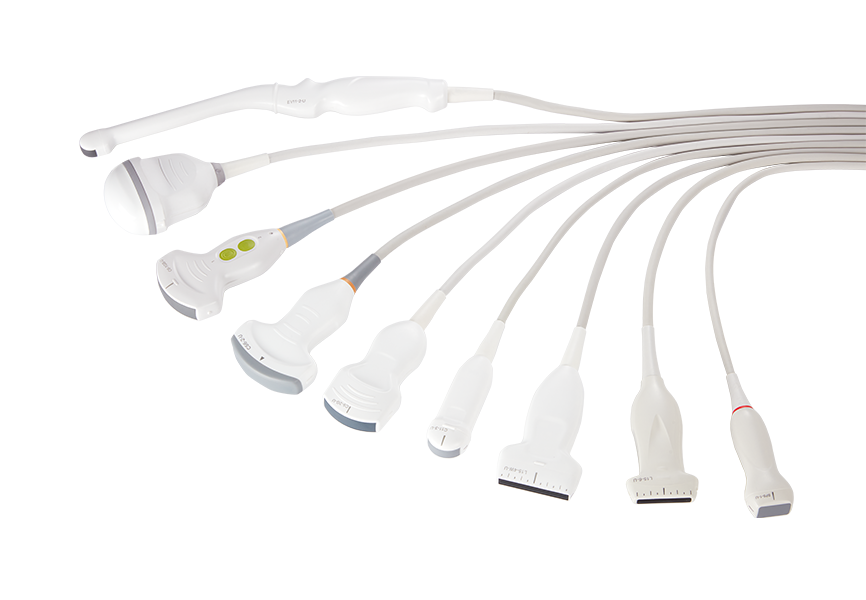

Plateforme CS de pointe dotée d'une technologie d'imagerie super-résolution unique dans l'industrie

Conceptions ergonomiques et flux de travail d'IA efficace, offrant une expérience utilisateur extraordinaire